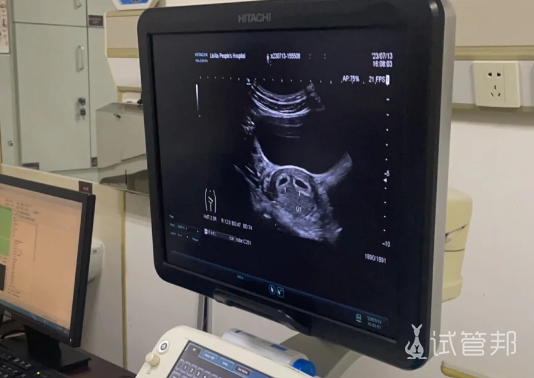

历经一年半的备孕,我从78斤增重至92斤,终于怀上宝宝。躺在检查床上,医生告诉我怀的是双胞胎,我愣住了,随即泪水涌出。一直期盼的小生命,一下子来了两个,我激动不已。没想到的事,两周后的复查,却被告知又分裂了一个,我瞬间愣住,难以置信。经过医生反复确认,竟是三个!

我们被告知需要转到省医院,于是,在天还没亮的时候,我们怀着忐忑的心情出发了。再次确认是三个宝宝后,我们夫妻俩在检查室外抱头痛哭。医生说,以我161的身高、92斤的体重,不适合怀三胞胎,建议我们减胎。那一刻,我感觉天都要塌了。

面对种种风险,我们面临艰难抉择,医生给出了三个方案。每个方案都充满不确定性,让我们左右为难。最终,我们还是希望能将三个宝宝都留下,但医生明确表示,我的身体条件难以坚持到孕晚期。12周前的每次产检,都是一场心理煎熬,孕吐严重到吐血,体重降至74斤。幸运的是,12周那天孕反突然结束,接下来的孕期变得轻松舒适。

经历了种种坎坷,我们迎来了nt检查,发现C胎儿数值异常。在十六周时,我们下定决心减胎。但第一次感受到强烈的胎动,我们坚定了留下的决心。羊穿结果显示一切正常,我们欣喜若狂。孕早期和孕中期虽然备受折磨,但18周后的每一天都过得轻松愉快。除了两个月的孕吐,我没有出现任何不适,体重从74斤增至116斤。